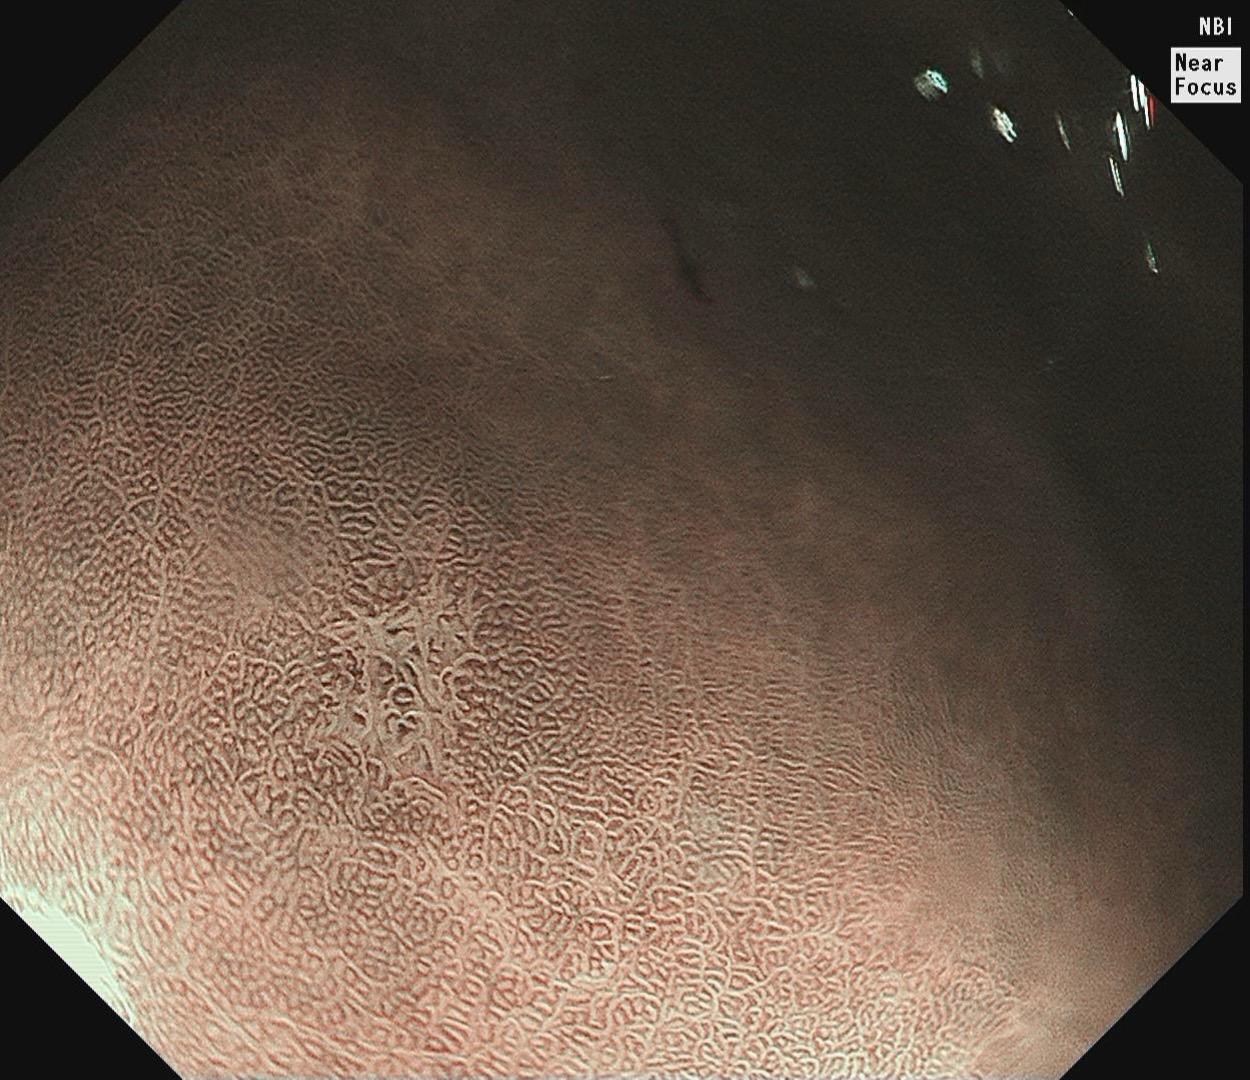

结肠SSL 醋酸染色。染色效果不亚于靛胭脂,结合NBI,Near fo...